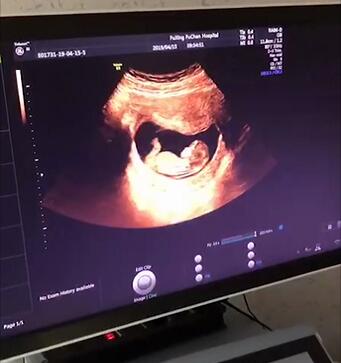

孕22-26周 四维彩超

这个时期,最主要的胎儿畸形筛查方法就是四维彩超检查。

它可以通过清晰的画面对胎儿的体表进行检查,

及时发现胎儿头颅、脊柱、心脏、胎盘、骨骼等异常情况。

双胎建议在20-24周进行检查。